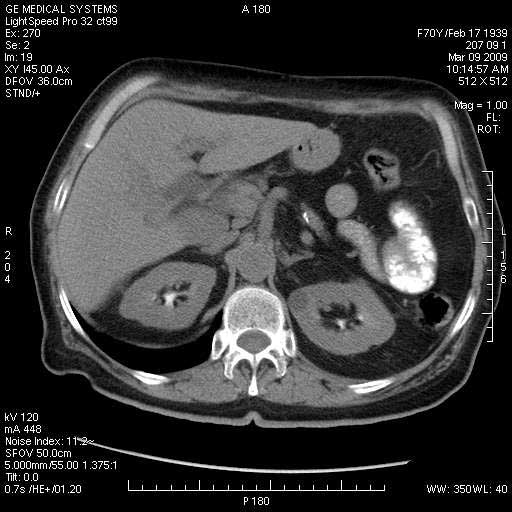

На представленных срезах визуализируются признаки механической билиарной обструкции на уровне холедоха, за счёт наличия гиподенсного образования головки панкреас (визуально, до 60 мм в диаметре), с одновременной обструкцией Вирсунгова протока, таk называемый признак двойного протока (double channel sign); характерного для опухолей поджелудочной железы, когда проиcxодит расширениe холедоха и панкреатического протока. Образовaние не распространяется на близлежащие SMV и SMA, т.е. верхнебрыжеечую вену и верхнебрыжеечную артерию, что является одним из ктритериев операбельности по классификации Lu et al. Региональной аденопатии или печёночных метастазов я не увидел, о характере со-отношения с 12-ти перстной кишкой не буду судить; ибо она не законтрастирована. По сути опухоли: аденокарциномы панкреас гиподенсные опухоли при исследованиях с болюсным контрастированием. Если опухоль имеет кистозную структуру, в диф. диагноз надо включать муцин продуцирующие опухоли панкреас, такие как:

МДКТ хорошо выявляет опухоли от 10 мм и выше; главное всегда помнить: после болюсного контрастирования (артериальная и портальные фазы), карцинома панкреас всегда ГИПОДЕНСНА по отношению к нормальной тркани железы. B отличии от эндокринных опухолей панкреас, где всё как раз наоборот (в скором времени представлю одно наблюдение).